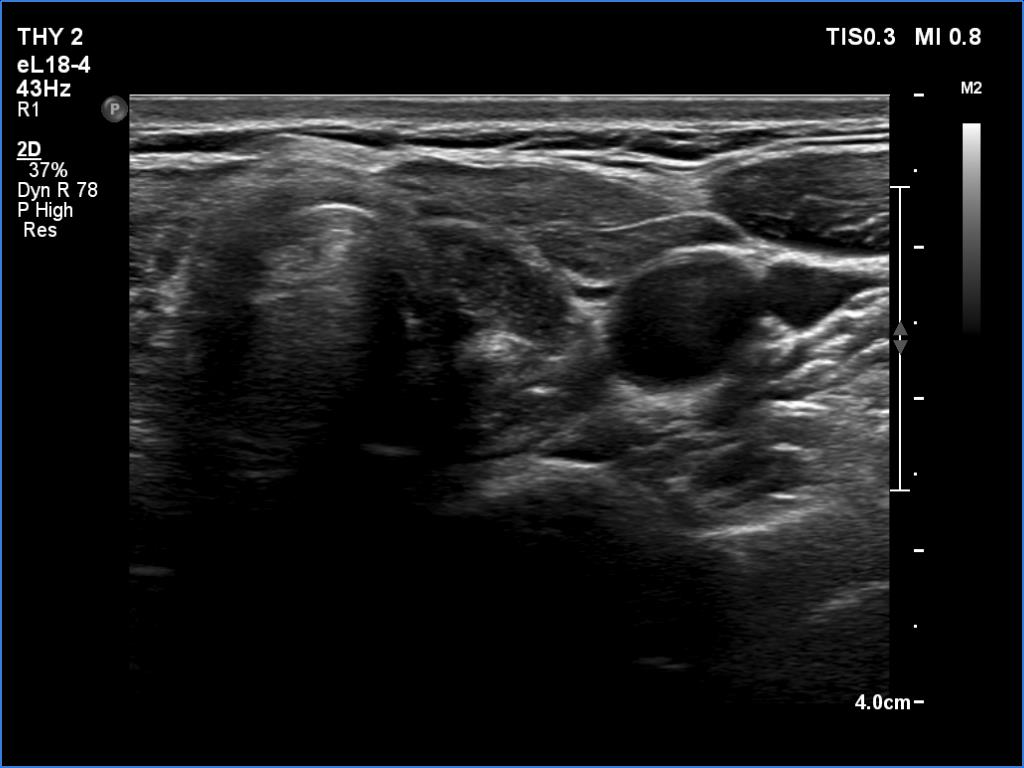

Ultrasonography. The thyroid was atrophic and deeply hypoechoic. The dimensions were 8x9x18 and 10x7x21 mm (width x depth x length), right and left lobe, respectively.

Comment. Most of the time, the atrophy seen here can be found in a long-standing hypothyroidism; in this patient, the thyroid volume has decreased to less than a tenth in 20 years.